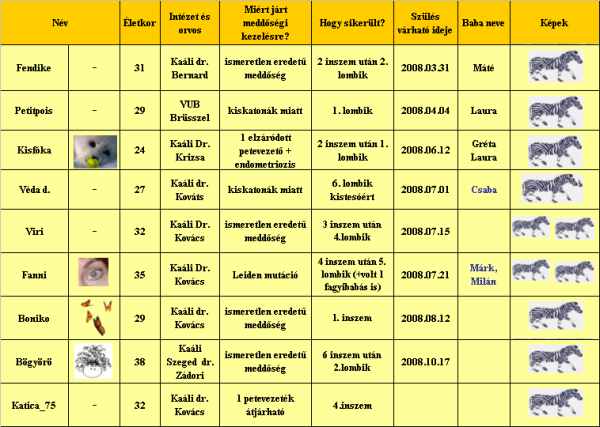

egy kép nektek

egy kép nektek